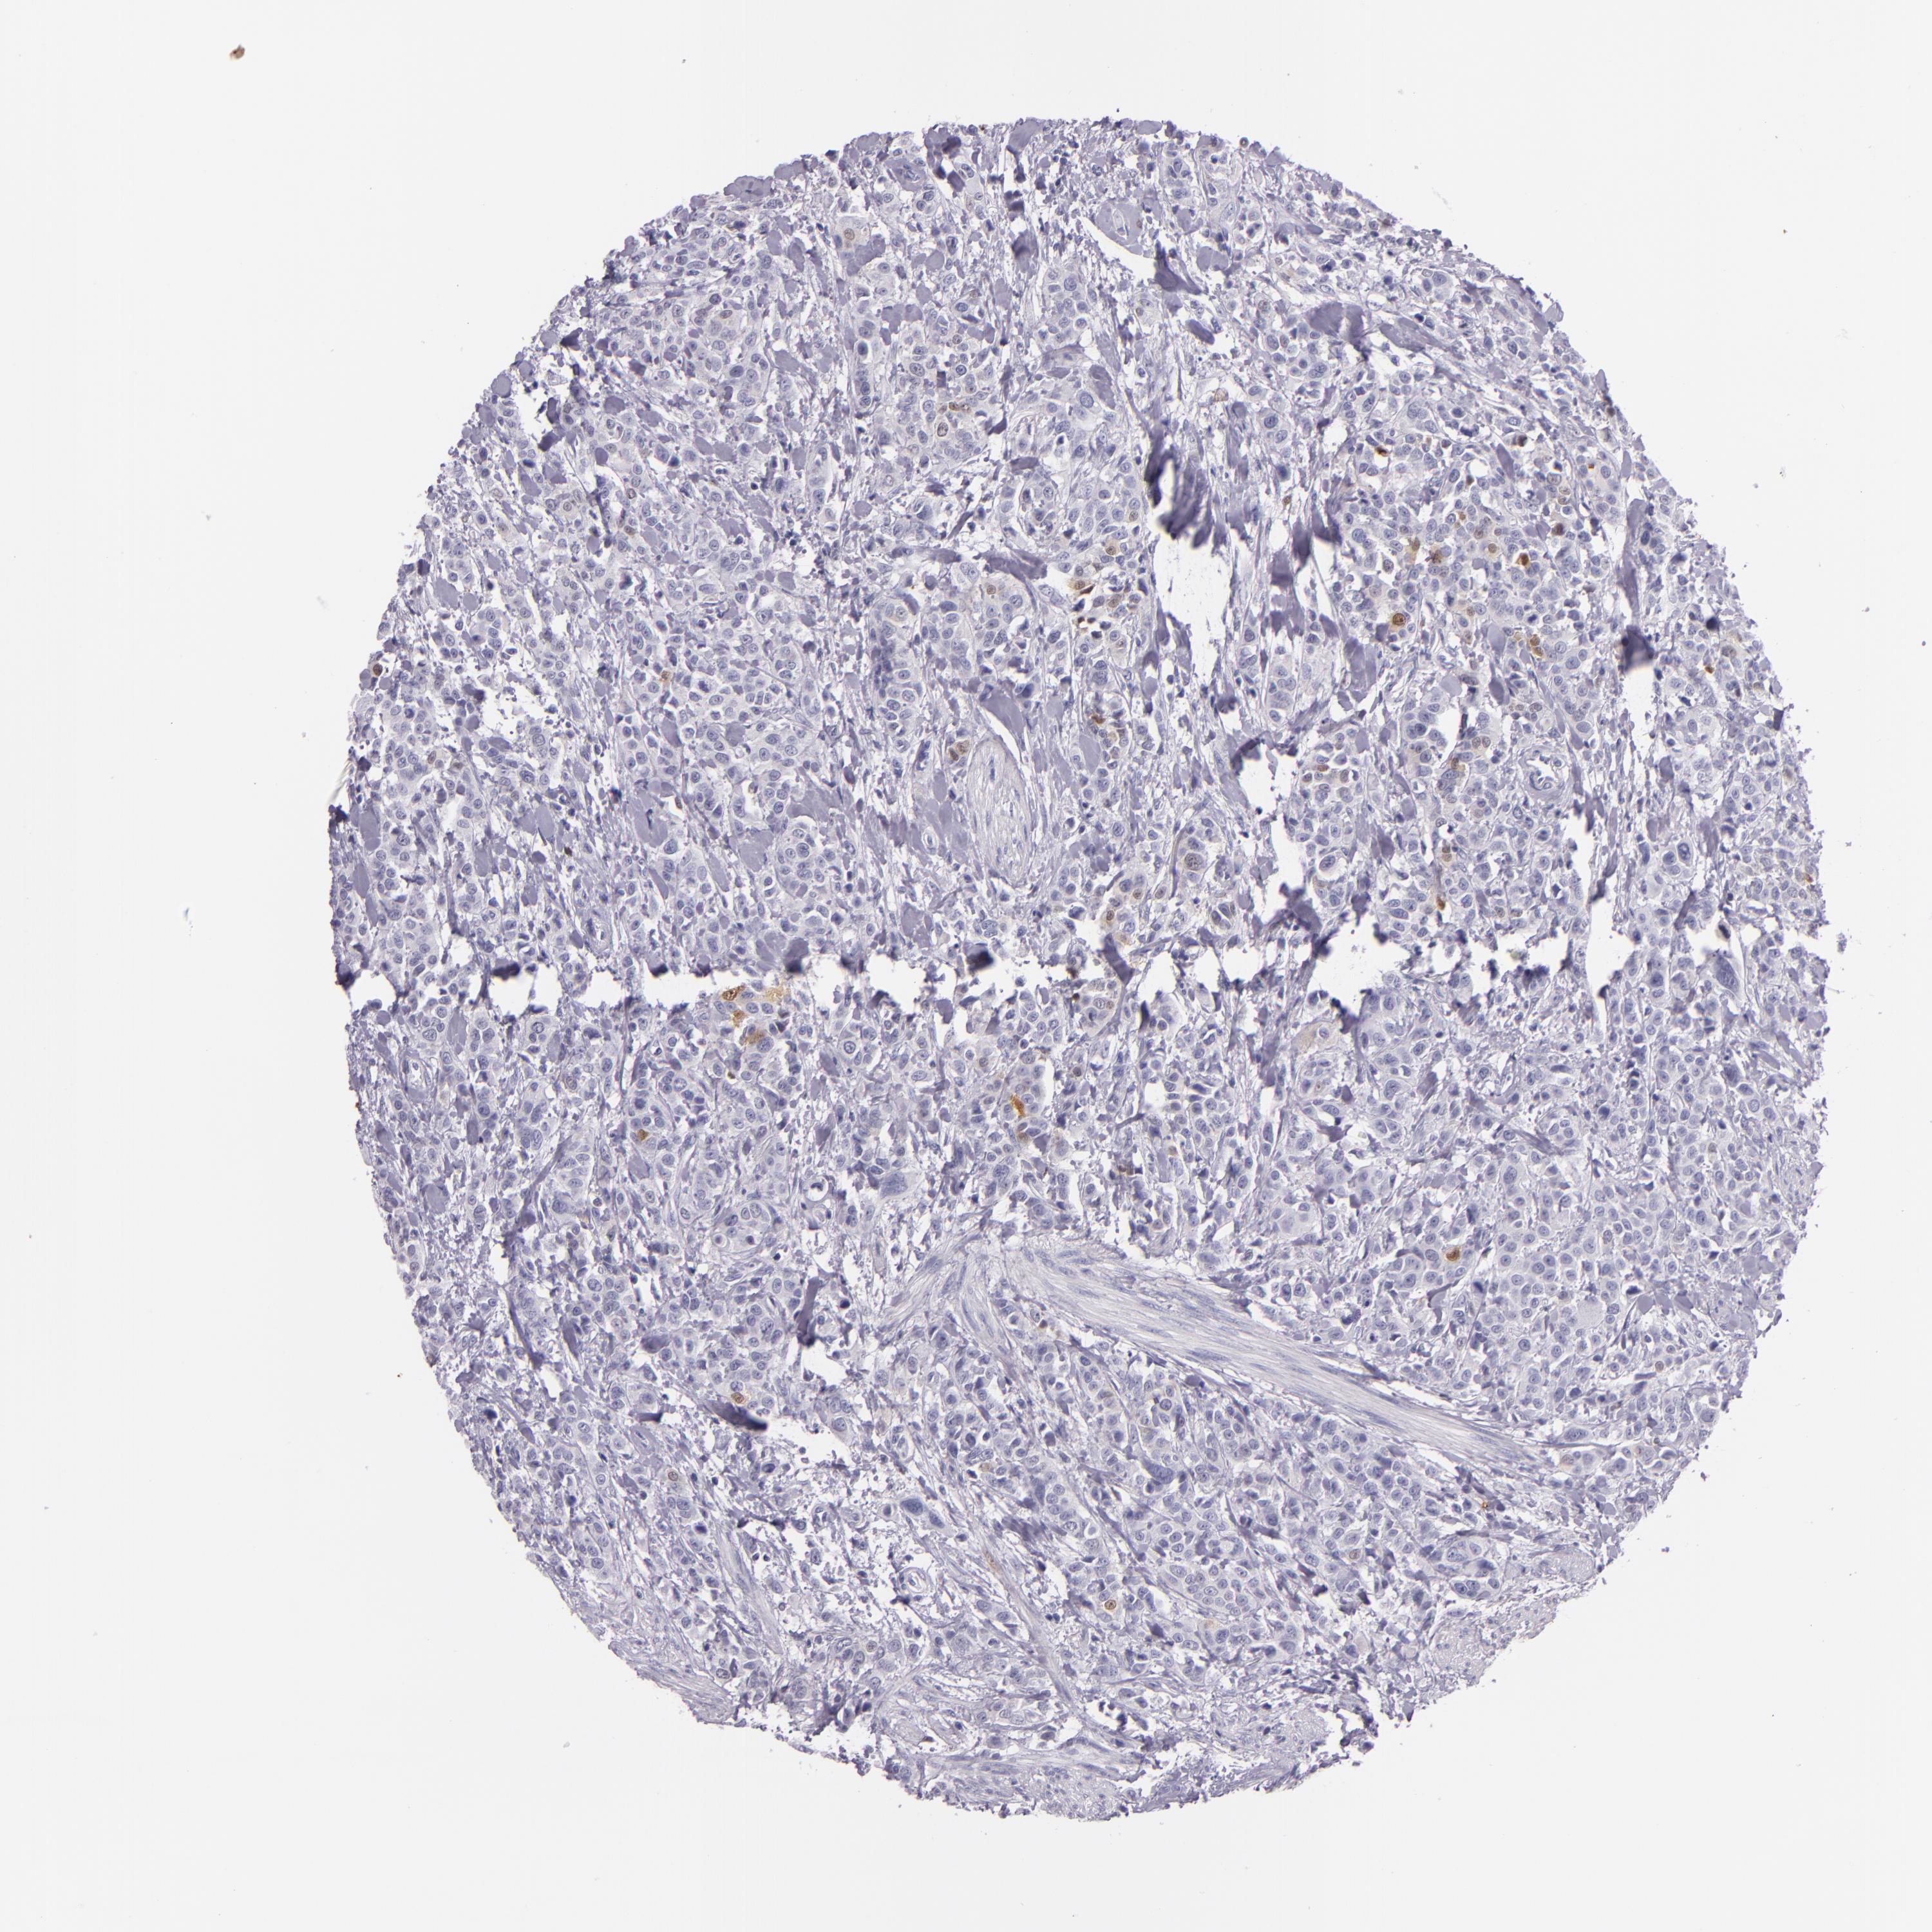

UROTHELIAL CANCER - Protein expressioni

A mouse-over function shows sample information and annotation data. Click on an image to view it in a full screen mode. Samples can be filtered based on level of antibody staining by selecting one or several of the following categories: high, medium, low and not detected. The assay and annotation is described here.

Antibody stainingi

Antibody staining in the annotated cell types in the current human tissue is reported as not detected, low, medium, or high, based on conventional immunohistochemistry profiling in selected tissues. This score is based on the combination of the staining intensity and fraction of stained cells.

Each image is clickable and will lead to virtual microscopy that enables deeper exploration of all samples and also displays staining intensity scores, fraction scores and subcellular localization as well as patient and tissue information for each sample.

Antibody CAB002161

Antibody CAB013056

Urothelial carcinoma, High grade

Urothelial carcinoma, Low grade

Adenocarcinoma, NOS